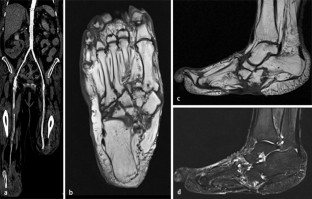

Abb. 1

Zur Ermittlung der Knochendichte stehen 2 State-of-the-art-Verfahren zur Verfügung: „dual energy X-ray absorptiometry“ (DXA) und quantitative Computertomographie (QCT). Für die Diagnostik von Insuffizienzfrakturen stehen Projektionsradiographie, Multidetektorcomputertomographie (MDCT) und Magnetresonanztomographie (MRT) zur Verfügung.

There are two state of the art imaging methods for the quantification of fracture risks: dual energy X-ray absorptiometry (DXA) and quantitative computed tomography (QCT). Radiography, multidetector computed tomography (MDCT) and magnetic resonance imaging (MRI) are suitable for the detection of insufficiency fractures.